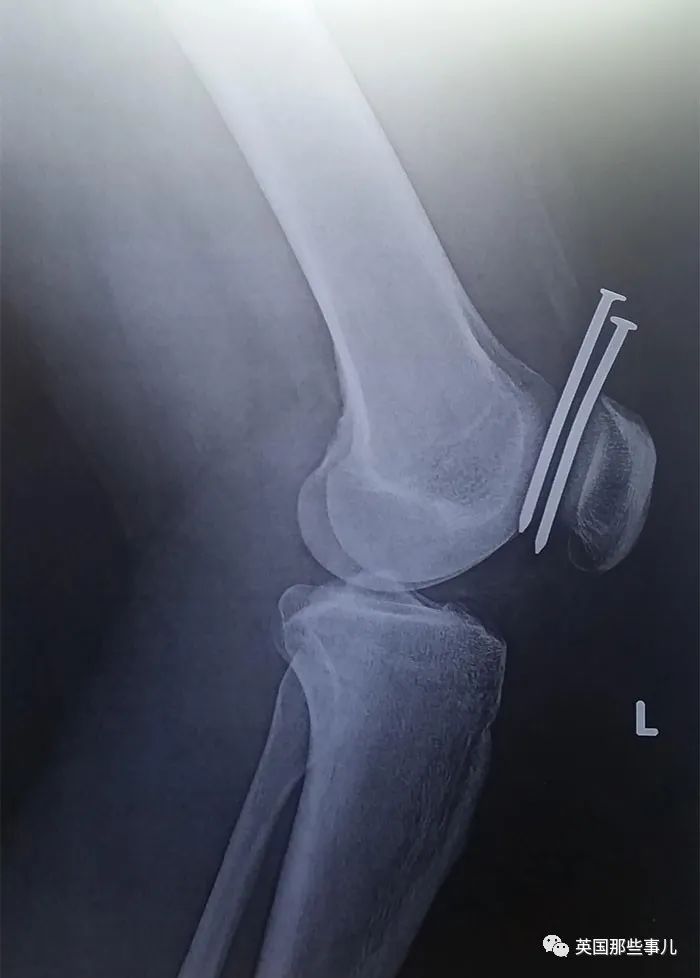

這人的腿被釘槍射中兩(liang) 次,每次都完美錯過股骨和膝蓋骨